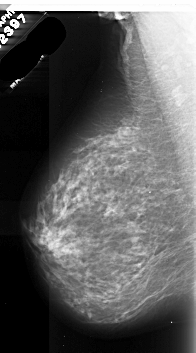

A_1087_1.RIGHT_MLO

LEFT_MLO LINES 6691 PIXELS_PER_LINE 3706 BITS_PER_PIXEL 16 RESOLUTION 42 NON_OVERLAY